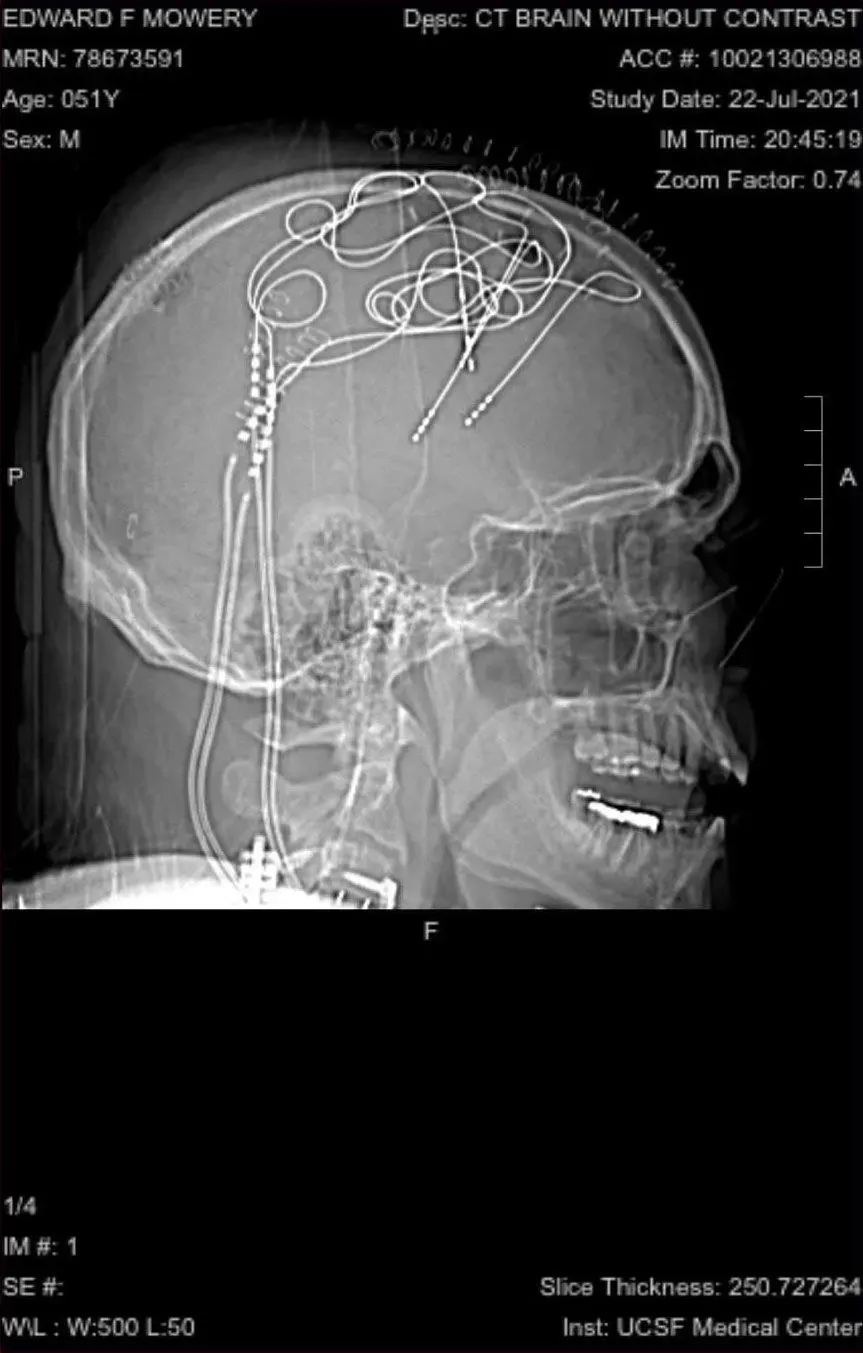

في الجراحة الأولى، سيضع الأطباء خريطة لدماغ موري لتحديد مصدر الألم. ستزيل جراحة أخرى المجسات المؤقتة من الإجراء الأول. وفي إجراء أخير تم وضع مجسات دائمة في المناطق الصحيحة.

بالنسبة للجزء الأول من التجربة، أمضى موري 10 أيام في المستشفى بينما كان الأطباء يضعون شبكة من أكثر من 100 نقطة على رأسه لمحاولة إيجاد دوائر مختلفة أو تنشيط معين للألم من خلال مراقبة دماغه وتحفيزه. وحتى مع قضاء ثمانية إلى عشرة أيام في سبر دماغه، لم يحظ الباحثون بـ "لحظة اكتشافهم" حتى اليوم الخامس أو السادس.